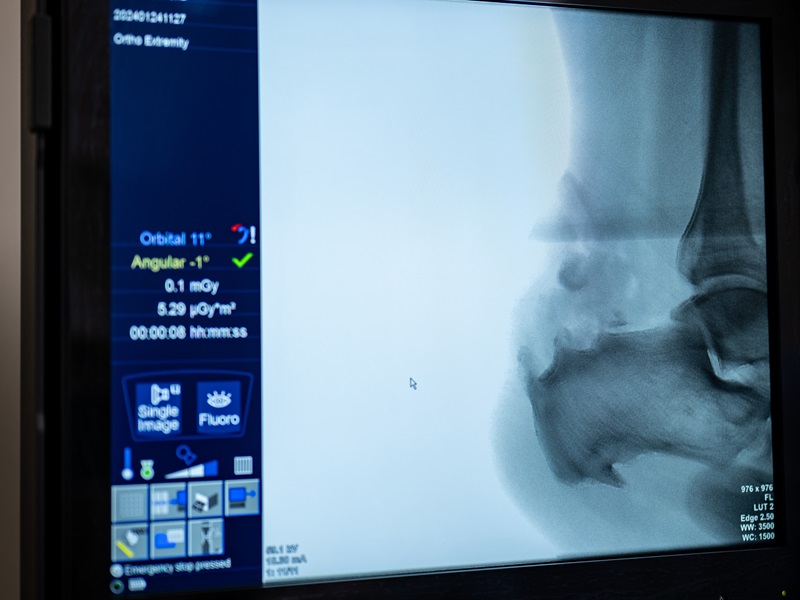

Діагностика хвороби Хаглунда

Із симптомами, схожими на ознаки деформації Хаглунда, потрібно звернутися до ортопеда-травматолога. Лікар проведе огляд, збере анамнез та призначить інструментальні дослідження — рентгенографію, УЗД або МРТ. Для встановлення діагнозу важливо відрізнити хворобу Хаглунда від запалення ахілова сухожилля, яке може розвиватися без утворення бугра п'яткової кістки.